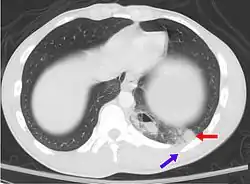

Un scanner montrant une contusion pulmonaire (rouge) accompagnée d'une fracture des côtes (bleue).

Une contusion pulmonaire est une ecchymose du poumon causée par un traumatisme thoracique.